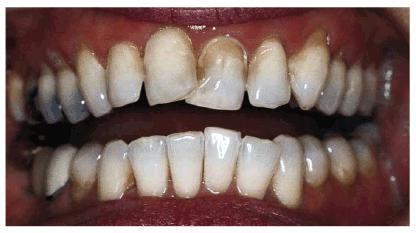

PROBLEM: This 30-year-old horse trainer had extremely large central

incisors (Figure 24-3A). In addition, the mandibular

centrals were crowded and rotated lingually (see Figures 24-3A, and 24-3B

Figure 24-3A: This 30-year-old woman had extremely large central incisors with overlapping maxillary and mandibular teeth.

Figure 24-3B: An occlusal view showing the overlapping central incisors.